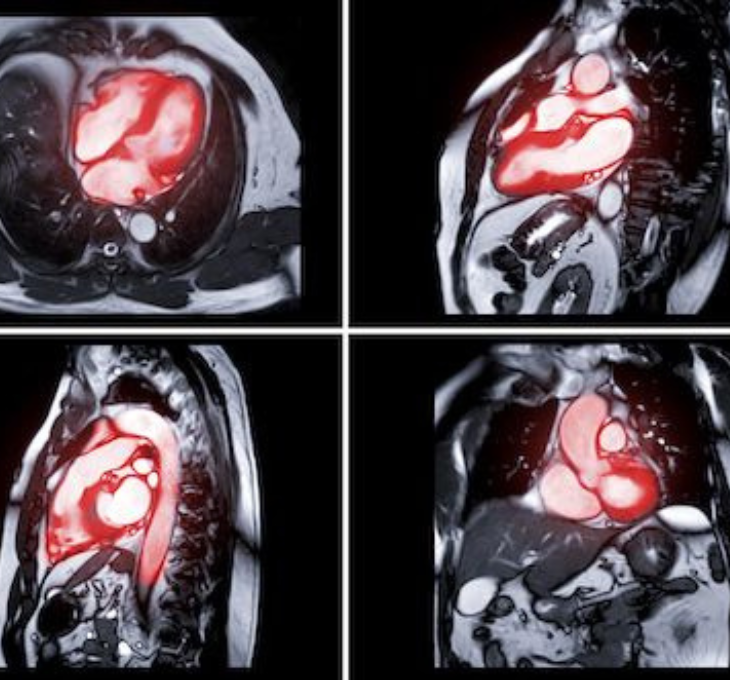

Myocardial Perfusion (Heart) Scan

Provides a three-dimensional image of the heart to assess blood flow under stress and resting conditions. Special instructions are provided for this study, and patients may remain in the department for up to five or six hours.